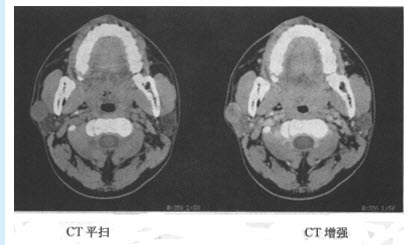

患者,女,32岁。右眼视物模糊3年余,影像学检查如下图。

(单选题)该患者最有可能的诊断是()

A:腮腺腺样淋巴瘤

B:腮腺混合瘤

C:腮腺神经鞘瘤

D:腮腺基底细胞瘤

E:腮腺囊肿